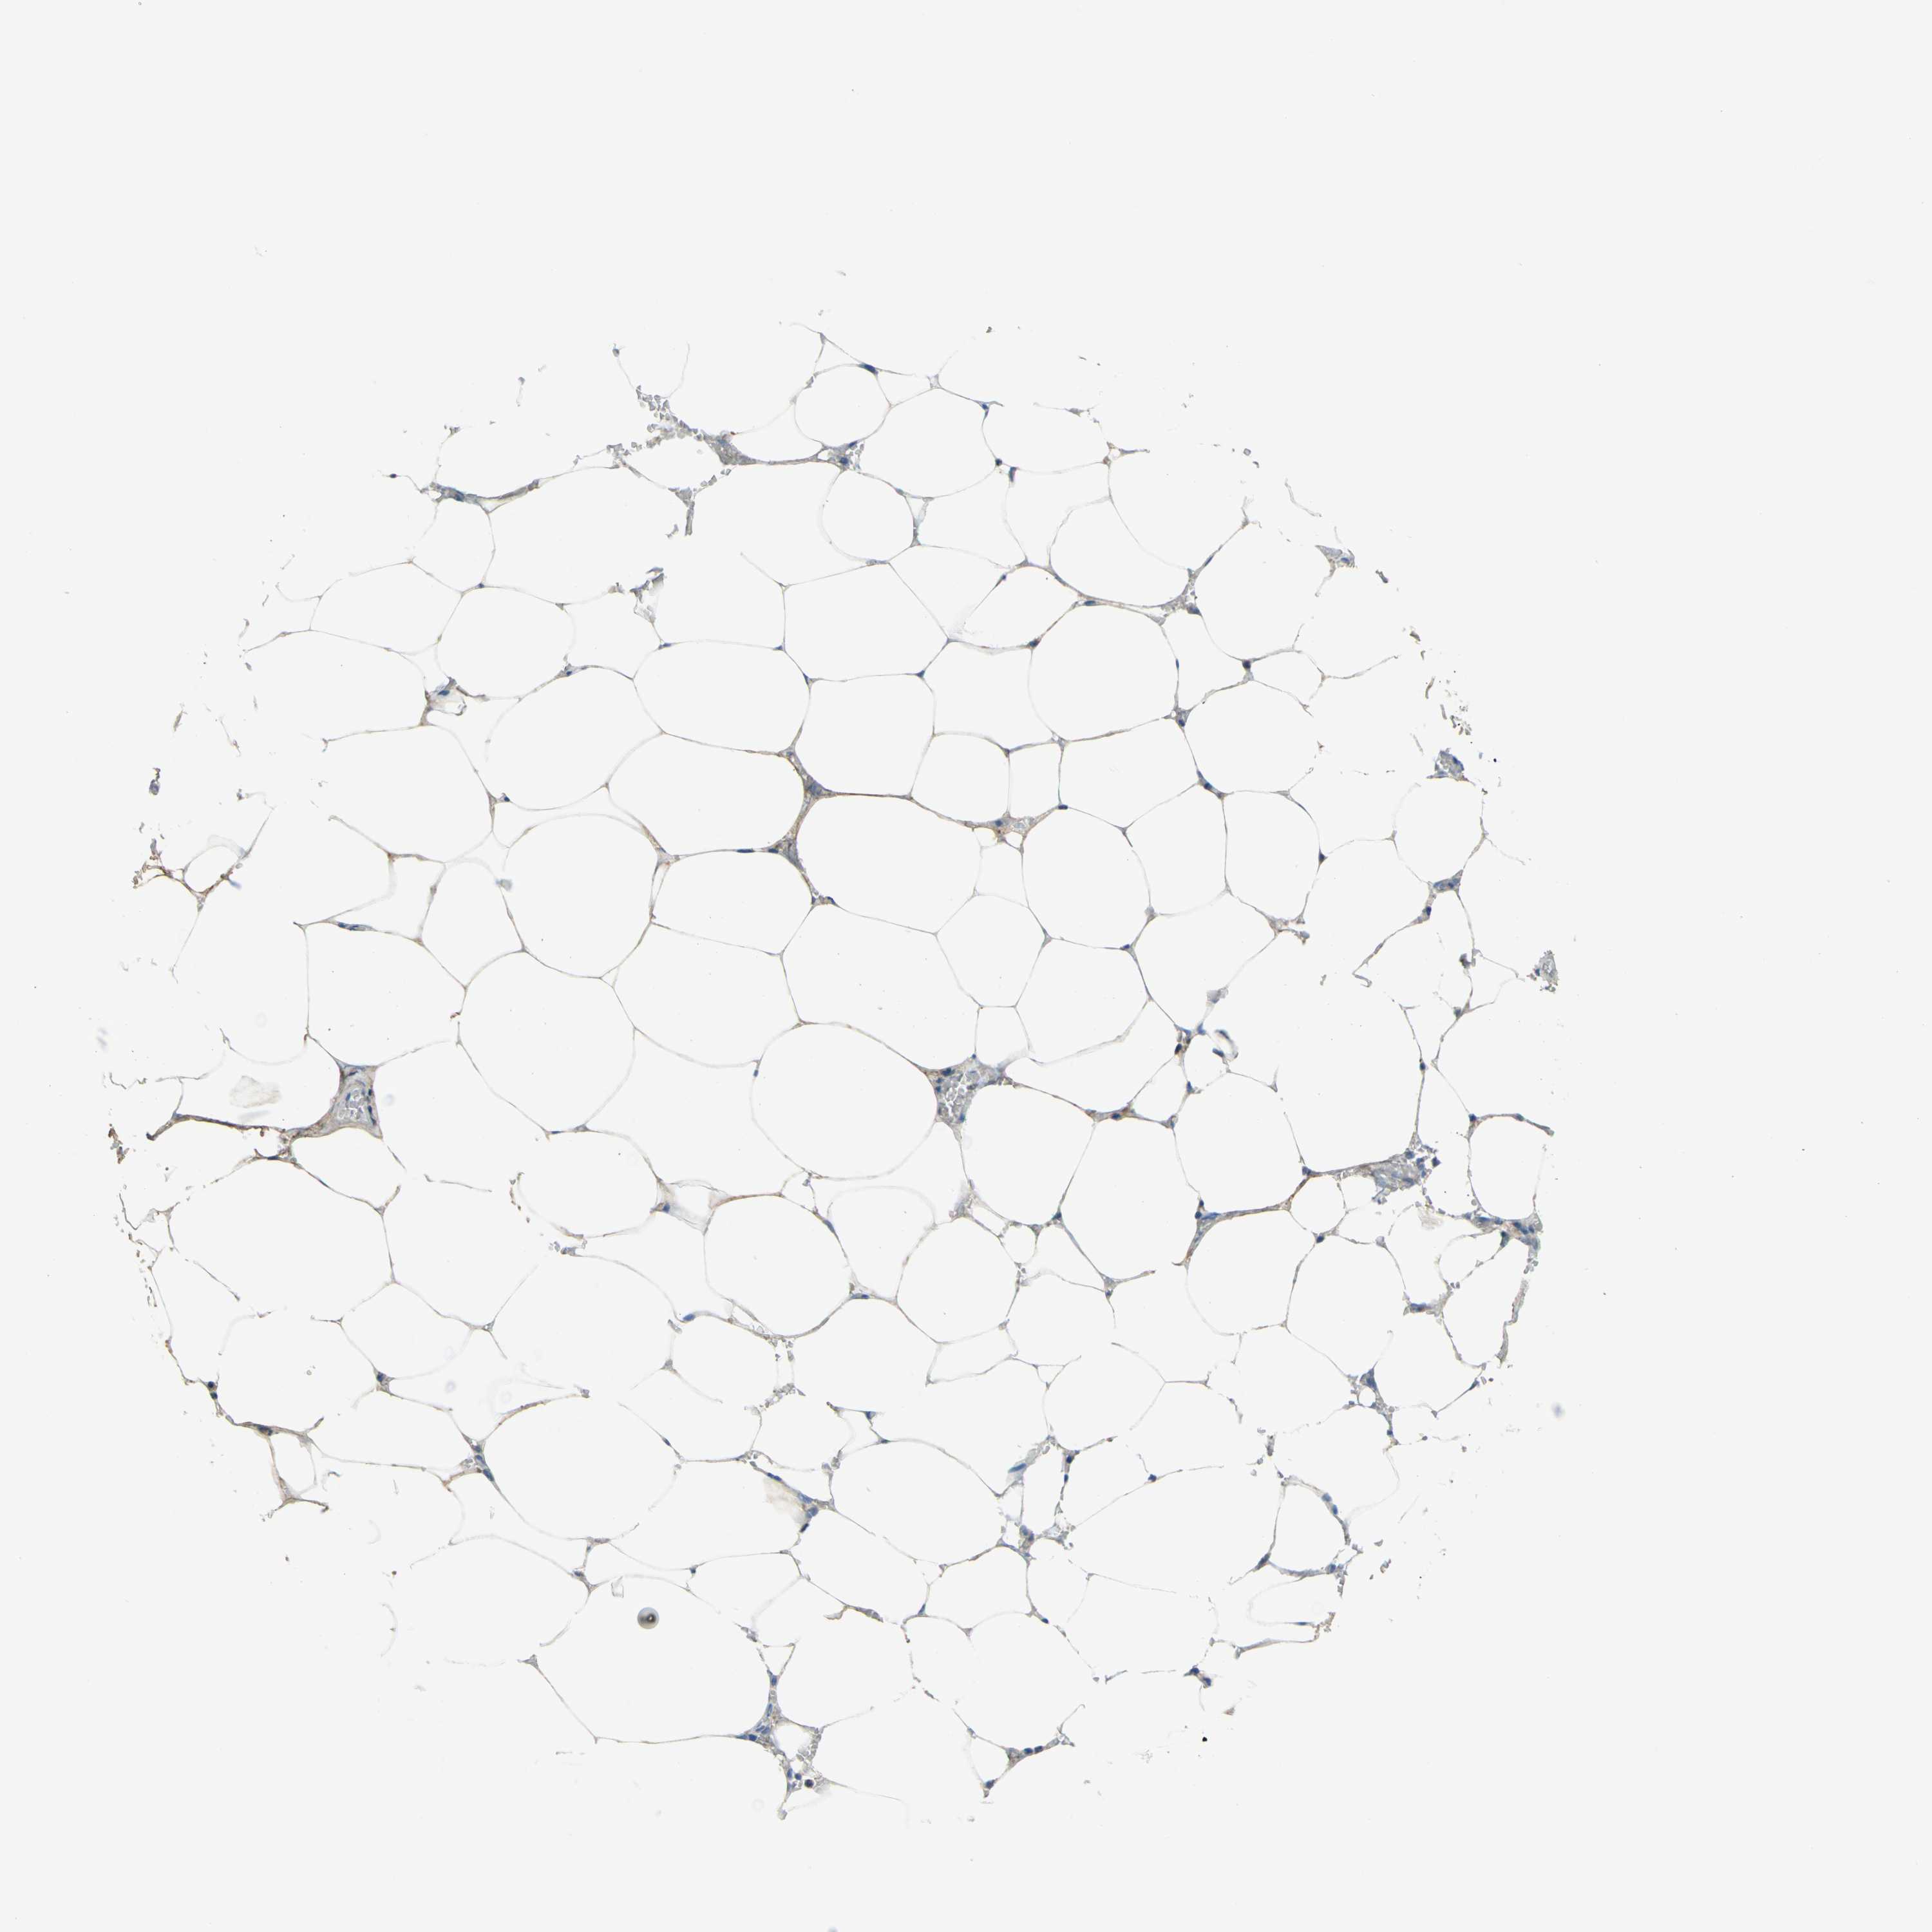

PANCREATIC CANCER - Protein expressioni

A mouse-over function shows sample information and annotation data. Click on an image to view it in a full screen mode. Samples can be filtered based on level of antibody staining by selecting one or several of the following categories: high, medium, low and not detected. The assay and annotation is described here.

Note that samples used for immunohistochemistry by the Human Protein Atlas do not correspond to samples in the TCGA dataset.

Antibody stainingi

Antibody staining in the annotated cell types in the current human tissue is reported as not detected, low, medium, or high, based on conventional immunohistochemistry profiling in selected tissues. This score is based on the combination of the staining intensity and fraction of stained cells.

Each image is clickable and will lead to virtual microscopy that enables deeper exploration of all samples and also displays staining intensity scores, fraction scores and subcellular localization as well as patient and tissue information for each sample.

Antibody HPA013132

Staining

High

Medium

Low

Not detected

Intensity

Strong

Moderate

Weak

Negative

Quantity

>75%

75%-25%

<25%

None

Location

Nuclear

Cytoplasmic/membranous

Cytoplasmic/membranous,nuclear

Adenocarcinoma, NOS